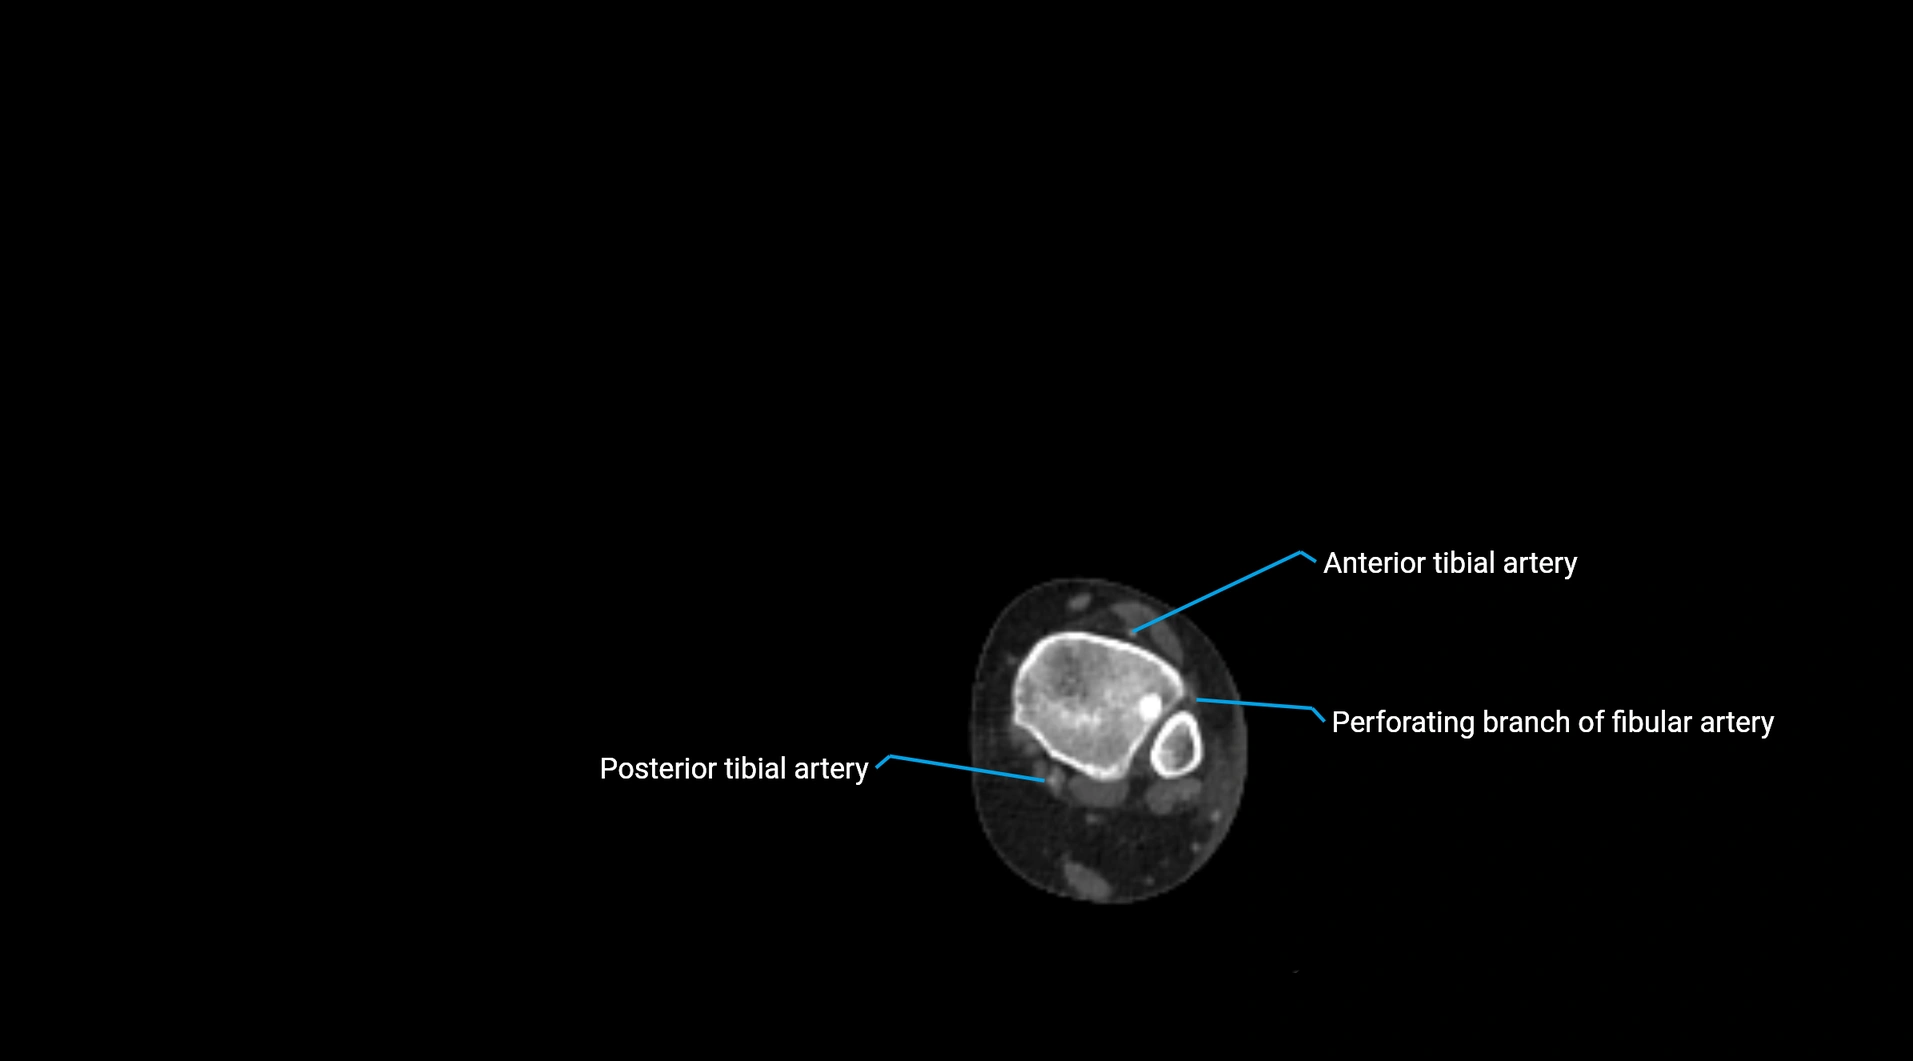

CT images

image

Contrast-enhanced CT (CTA):

• Gold standard for abdominal aortic imaging

• Provides excellent detail of lumen, wall, aneurysm, thrombus, and branch vessels

• Multiplanar and 3D reconstructions help in aneurysm measurement, stent graft planning, and dissection evaluation